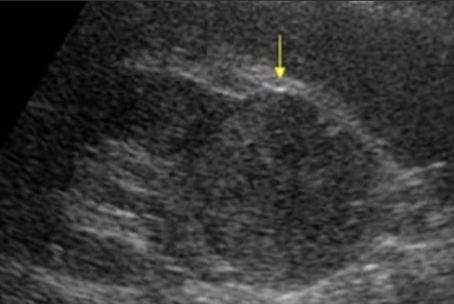

complex mass

shows characteristics of both cystic and solid lesions

may contain septations, thick walls > 1 mm, nodularity, calcifications, internal echoes from areas of necrosis, hemorrhage, or abscess/infection

** if there is septation in cyst, put color box on it, especially if its thick

describe

“complex structure measuring 3 cm x 3 cm x 3 cm noted in UP/MP LK. vascularity noted within”

complex cyst

may contain septations, thick walls, calcifications, internal echoes, and mural nodularity

considered malignant until proven benign, especially if septa >1 mm thick with vascular flow on color or Power Doppler

any irregularity at the base of the cyst should be considered a malignant growth

??

has septations and solid components